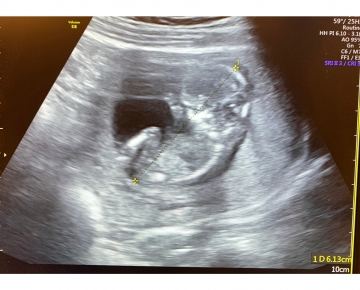

34歲低AMH集胚2次約半年成功懷胎